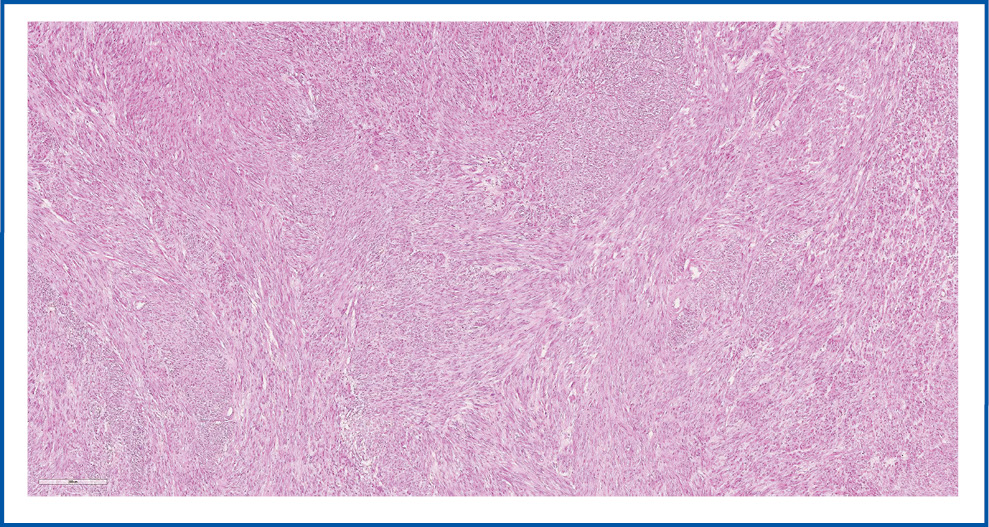

Гистологическое исследование: в ТМ определяются множественные четкие беловатые узлы, плотноэластической консистенции, на разрезе слоистые. Микроскопически хорошо очерченные множественные узлы с четкими границами, представленные переплетающимися пучками мономорфных удлиненных веретенообразных клеток с обильной эозинофильной цитоплазмой, ядрами овальной формы, незаметными ядрышками. Некроз, фигуры митозов и сосудистая инвазия в опухоли не определяются. Установлен диагноз многоузловой ЛММ (рис. 1).

Рис. 1. ЛММ. Окраска гематоксилин-эозином, ×20.

Fig. 1. Uterine leiomyoma (ULM). Hematoxylin and eosin staining, ×20.